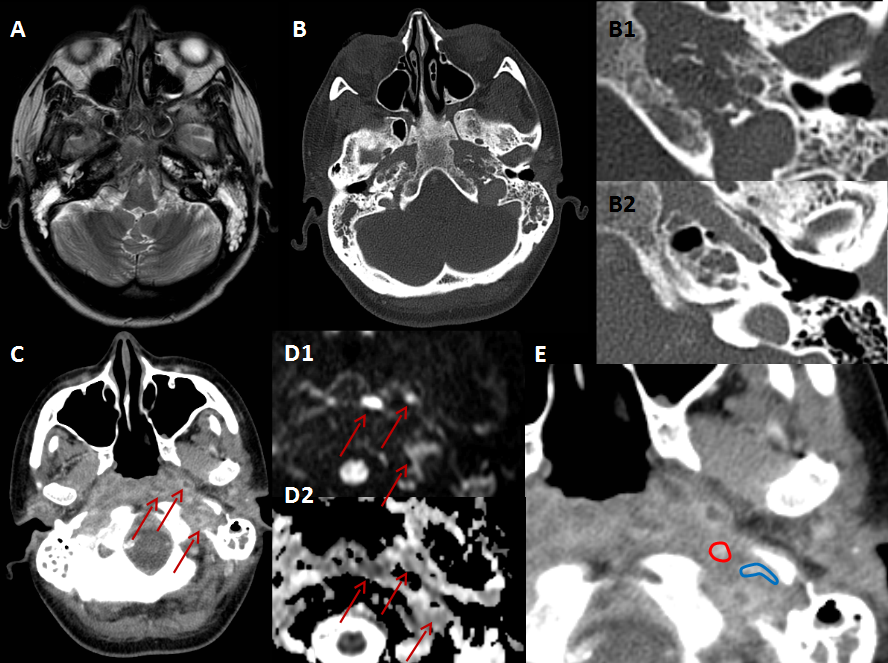

A: T2, axial: Ocupación de ambas cajas timpánicas y celdillas mastoideas, en relación con cambios inflamatorios otomastoideos bilaterales.

B: TC, axial: Ocupación de las celdillas del ápex petroso. B1: Imagen detallada donde se identifican erosiones óseas en el ápex. B2: Comparación con estudio previo de la misma paciente 3 meses antes, donde las celdillas se encontraban completamente íntegras.

C: TC, axial: Realce difuso de los tejidos blandos de la base de cráneo con presencia de varias colecciones hipodensas con realce periférico en nasofaringe, en el espacio parafaríngeo y carotídeo izquierdo.

D1: DWI; D2: ADC, axial ampliado: Las colecciones tienen alta señal en DWI y baja en el mapa ADC, es decir, restringen la difusión.

E: TC axial, imagen ampliada de C: La colección del espacio carotídeo izquierdo comprime la vena yugular interna (la carótida está rodeada en rojo y la yugular en azul).